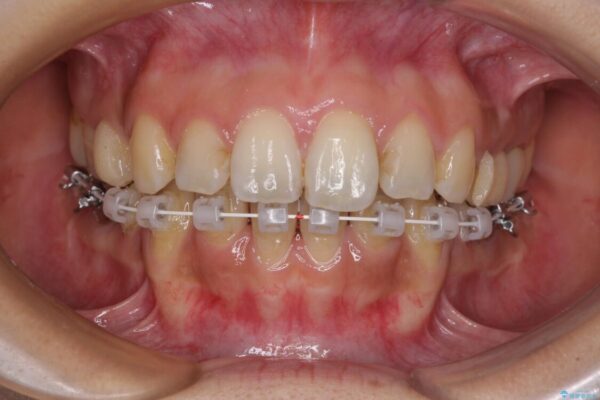

ハーフリンガル

目立たない装置を希望されたので、上顎が裏側装置のハーフリンガルを選択し、上下左右の小臼歯(計4歯)を抜歯して矯正治療を行うこととしました。

治療途中

• デコボコと口元の突出感 ハーフリンガルでの抜歯矯正 治療途中画像